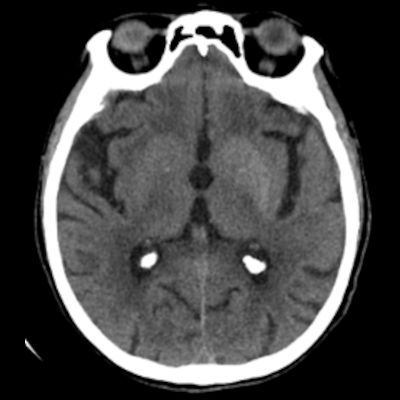

75 yaş, K

Sağ üst kolda atım şeklinde hareket

Tanınız nedir?

Nonketotik hiperglisemik hemikore

Diyabetik striatopati

Non-ketotik hiperglisemiye bağlı hemikore-hemibalizm

non-ketotic hyperglycemic hemichorea